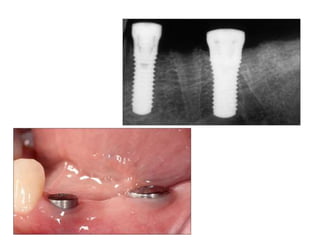

Implants require more precise impressions than crowns and bridges because implants lack a periodontal ligament to compensate for inaccuracies. It is critical to accurately record the three-dimensional position, angulation, and depth of implants to obtain a proper fitting definitive restoration. Making high quality impressions at the implant or abutment level is necessary to successfully fabricate implant prostheses.